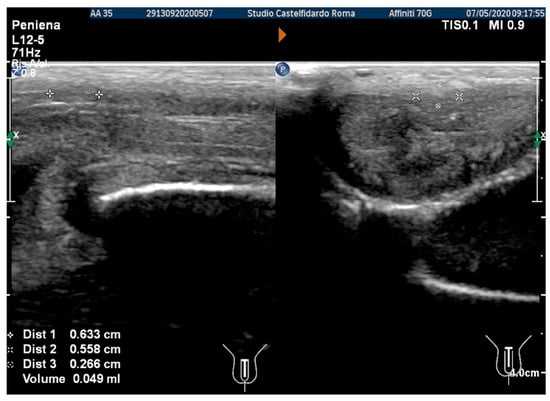

After the third treatment cycle, the patient underwent a similar follow-up with a physical exam and a penile Doppler ultrasound. The IIEF score was 27. We then observed a dorsal penile curvature of 15 degrees (unchanged). The penile ultrasound showed the following plaque dimensions: 4.95 × 3.91 × 2.02 mm (21 mm3 = volume) (Figure 12).

Figure 12. Ultrasonography of the penis after the 3rd therapy cycle. (A) Longitudinal view; (B) axial view.